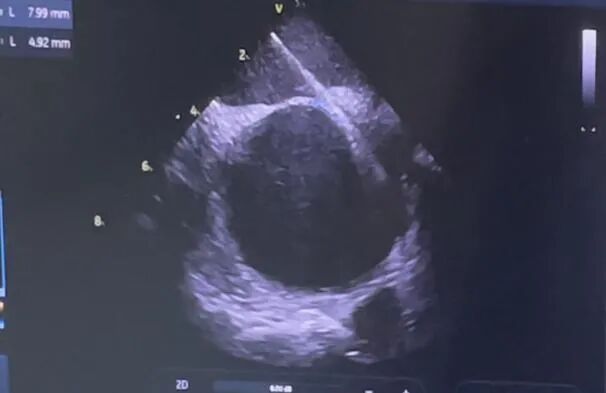

术前超声

手术在ICE引导下开展,经“右股静脉-右房-PFO-左房”成功建立工作轨道,于ICE指引下精准过隔,并进一步观察PFO结构。术中精确测量卵圆孔直径为4.92 mm、隧道长度为7.99 mm,遂沿路径于ICE引导下送入一枚28mm×28mm MemoSorb®生物可降解PFO封堵器至卵圆孔未闭处,并遵循一贴、二扣、三锁、四剪、五撤的规范化5S操作步骤,确保封堵器双盘骑跨于缺损左右两侧,牵拉成型线使封堵器双盘扣合住卵圆窝、呈“工”字型,随后经造影与ICE反复确认封堵器位置稳固,形态良好,遂锁定封堵器,剪断并抽出成型线。术后超声示,封堵完全,未见残余分流,整个过程约37分钟,手术圆满成功。